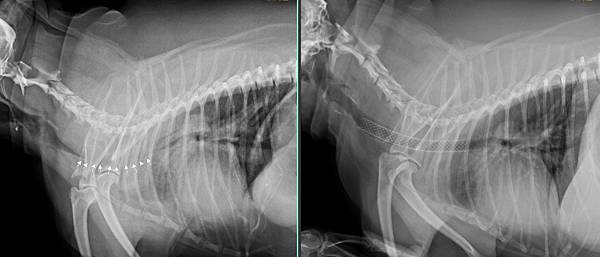

檢查發現嚴重的氣管塌陷

經過安裝人工氣管支架後

立刻恢復正常